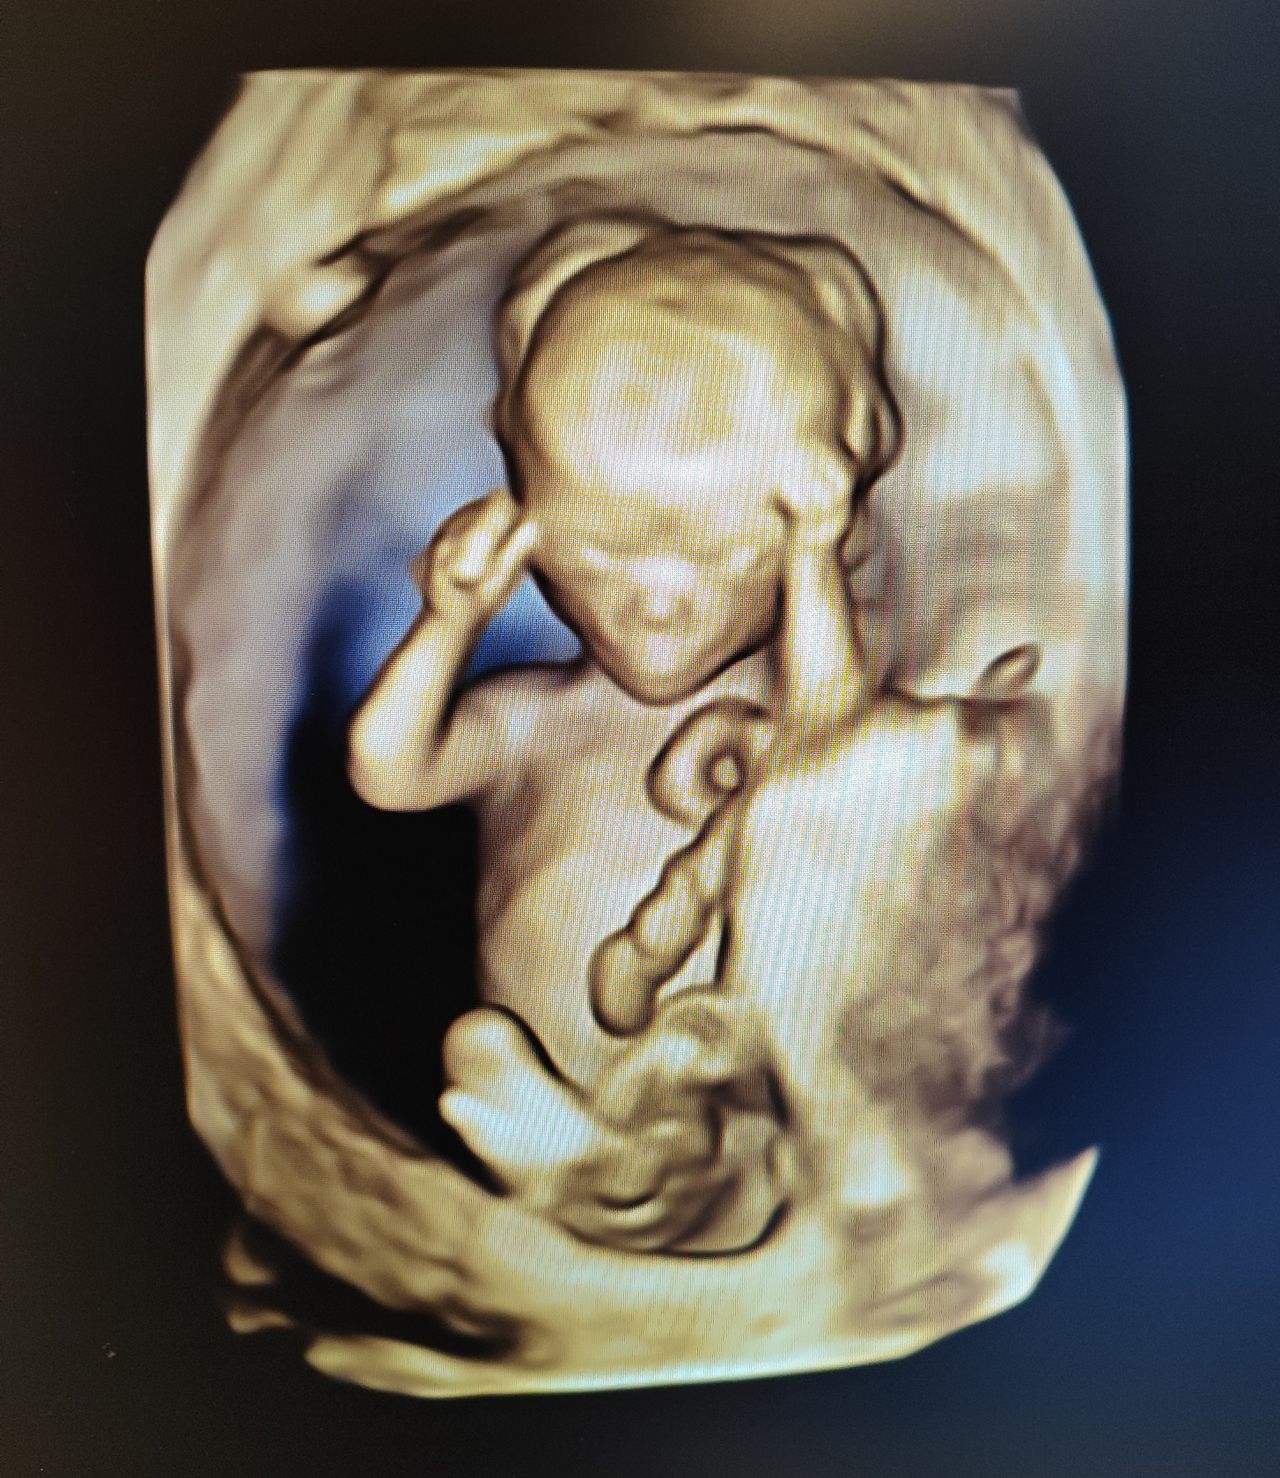

Dal 2015 al 2016 , frequenza presso U.O. Santa Maria delle Croci , Ravenna , periodo di Training di Chirurgia Laparoscopica, Endoscopica e di Isteroscopia ambulatoriale /office. In quell'anno nella stessa sede , ho  frequentato L'Ambulatorio di Diagnosi Prenatale acquisendo competenze in Ecografia Ostetrica del I-II-III trimestre.  Dopo la specializzazione ho proseguito la formazione e l'aggiornamento in particolare occupandomi dell’ Ecografia in ambito Ostetrico.

Ho acquisito "Certificate of Competence " da parte della Fetal Medicine Foundation per l'ecografia dell'11-13 settimana di gravidanza .

Da Maggio 2017 ad oggi faccio parte dello STAFF dell’Unità Operativa di Ostetricia e Ginecologia presso l’Ospedale "degli Infermi" di Faenza e dell’Ospedale "Morgagni Pierantoni "di Forli e mi occupo principalmente di Ostetricia , Gravidanza a Rischio, e dell'Ambulatorio Diagnosi Prenatale dove eseguo ecografie genetiche del I trimestre ed ecografie morfologiche e del III trimestre di gravidanza .